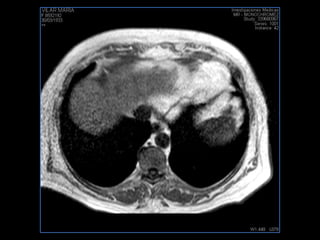

PROTOCOLO hemocromatosis AXIAL supresión grasa /AX multieco en higado COR T2 AX T1 +SAG T2  CON   GADOLINIO :  COR T1+AX T1 SAT: NO  FASE: RL THK: 4MM  COIL:  GAP: (FACTOR 1.4) 1MM FOV: 40 CM NEX:2 SINCRONIZACION RESPIRATORIA EN 3 O 4 CICLOS ALE